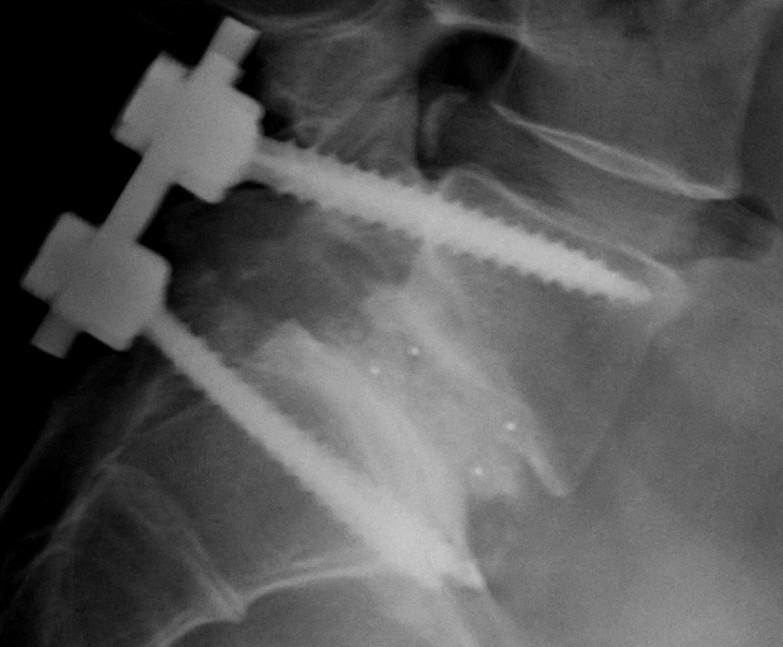

Before and after my scoliosis spinal fusion ) [OC] r/XRayPorn How Much Can You Lift After Spinal Fusion Patients may progress from walking to more demanding exercises, such as swimming. In most cases, strength training is completely off the table during the first three months after spinal fusion surgery. Recovery from spinal fusion surgery varies for individuals. Physical therapists typically propose adjustments to the work environment to help patients return to the workplace. It depends on the specific. How Much Can You Lift After Spinal Fusion.

I've had a spinal fusion done. It's actually one of the largest spinal How Much Can You Lift After Spinal Fusion Recovery from spinal fusion surgery varies for individuals. Depending on the nature of your fusion and curve, you might need. Patients may progress from walking to more demanding exercises, such as swimming. No matter what type of surgery a person has, most experts recommend avoiding lifting anything heavier than 10 lbs. You probably should not perform powerlifting exercises after spinal. How Much Can You Lift After Spinal Fusion.

Xrays of my spinal fusion surgery before and after r/pics How Much Can You Lift After Spinal Fusion Instead of endangering the fusion, exercising the area after 3 months helps it become stronger. In most cases, strength training is completely off the table during the first three months after spinal fusion surgery. Excess bending, lifting, and twisting are still to be avoided in most cases, but graduated exercise, as tolerated,. Recovery from spinal fusion surgery varies for individuals.. How Much Can You Lift After Spinal Fusion.